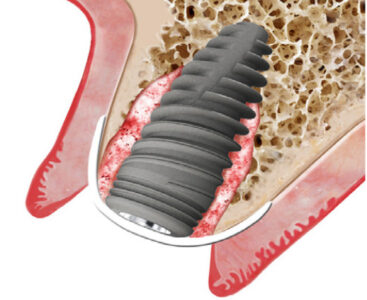

Zastosowania membran osierdziowych SHELTER S

•Regeneracja kości metodą „Sausage Technique”

•Wykonywanie zabiegów podniesienia zatok

•Pozioma i pionowa augmentacja

•Utrzymanie zębodołu i grzebienia kostnego

•Ubytki śródkostne (jedno, dwu lub trójścienne)

•Zamykanie ubytków po resekcji wierzchołka korzenia

Membrana o grubości 0,8 mm może z powodzeniem zastąpić membranę PTFE.Jej właściwości chemostatyczne gwarantują szybkie gojenie w przypadkach rozejścia pooperacyjnego. Zapewnia również tworzenie się nowych połączeń naczyniowych, umożliwiających odpowiednie ukrwienie tkanek.